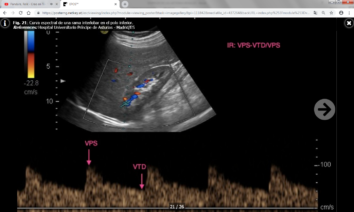

- Índice de resistencia (IR) : Es el resultado del cociente VPS – VTD / VPS (siendo VPS la velocidad picosistólica y VTD la velocidad al final de la diástole). Se debe calcular una media con las distintas medidas obtenidas en cada riñón y valorar si existen diferencias entre un riñón y el contralateral. Lo normal es que el índice de resistencia esté entre 0.6-0.7 y que la diferencia entre ambos riñones sea menor del 5% (ó 0.05). Un aumento de la velocidad telediastólica mayor de 150 cm/s en un paciente con IR intrarrenal menor de 0.7 es altamente sospechoso de estenosis mayor del 80%.

El IR no solamente permite detectar la presencia de estenosis significativas, sino que además predice el pronóstico y la respuesta al tratamiento de revascularización: En un estudio se publicó que en pacientes con IR mayores de 0.8 había escasa respuesta al tratamiento de revascularización ya que la enfermedad renal estaba establecida y era irreversible. No obstante, estos datos han sido ampliamente discutidos en la literatura y no existe acuerdo a día de hoy. - Tiempo de aceleración (TA) e índice de aceleración (IA) : Son parámetros más operador dependientes y por ello menos fiables que el IR. Los valores normales son menores de 0.07-0.08 ms y menores de 3 m/s respectivamente.